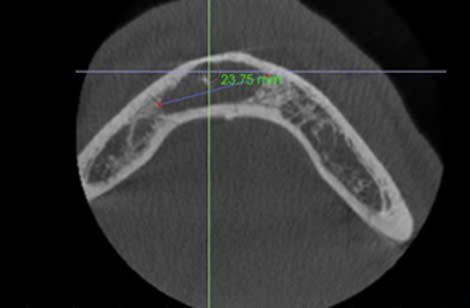

ĐIỀU TRỊ NỘI NHA KHÔNG PHẪU THUẬT ĐỐI VỚI CÁC RĂNG CÓ TỔN THƯƠNG QUANH CHÓP LỚN

Viêm quanh chóp là tổn thương viêm của các thành phần mô học vùng quanh chóp răng. Đây là kết quả của phản ứng viêm với sự xâm nhập của vi sinh vật và độc tố của chúng trong hệ...